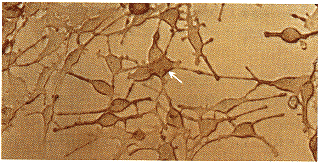

(一)8-MOP对B16F10细胞形态的影响:传代培养的B16F10细胞主要为两极,偶见三极的贴壁生长上皮型细胞,只有经多巴染色后才能在细胞浆内观察到多巴染色阳性的褐色颗粒存在(图1)。当细胞经50μmol/L或100μmol/L 8-MOP作用48 h后,即能发现细胞树状突明显增多并延长,胞浆和树状突内出现大量棕褐色颗粒,72 h后观察这些形态变化更加明显(图2)。

图1 B16F10细胞主要为两极,偶见三极的贴壁生长上皮型细胞,经多巴染色后在细胞浆内可见到多巴染色阳性的褐色颗粒(×400)

图2 B16F10细胞经50μmol/L 8-MOP作用48h后,见细胞树状突明显增多并延长,胞浆和树状突内未经多巴染色也可见到大量棕褐色颗粒(×200)